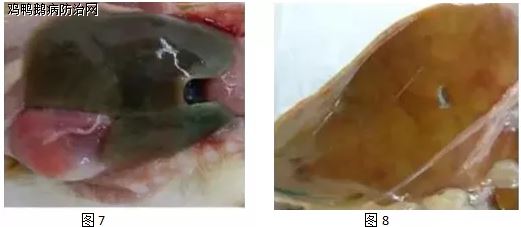

有的肝脏表面呈弥漫性点状出血(图1);有的肝脏表面呈弥漫性点状出血与“地图样”花纹坏死斑(图2);有的 肝脏表面布满大小不一的灰白色呈“雪花样”的坏死灶(图3);有的肝脏表面布满针尖至米粒大小的黄白色的坏死的与结节样隆起(图4);肝脏表面覆盖灰白色、半透明纤维素性膜,被膜下可见灰白色坏死点(图5);有的肝脏表面覆盖灰白色、半透明纤维素性膜,被膜下可见灰白色坏死点(图6);有的肝脏萎缩,外观呈绿色(图7);有的肝脏萎缩,外观呈黄绿色(图8);有的肝脏淤血,表面可见少量栗粒大小灰白色的坏死点(图9);有的肝脏肿大,质地脆弱,呈土黄色(图10);有的脾脏肿大,有绿豆大小灰白色坏死灶(图11);有的胆囊肿大,胆汁充盈,胆囊壁可见米粒大小白色的坏死点(图12);有的肾脏肿大,表面可见米粒状灰白色坏死性结节(图13);有的肾脏肿大、苍白(图14);有的胰腺可见中间透明样的灰白色坏死灶(图15);有的卵泡充血、变形、变性、甚至破裂(图16)。